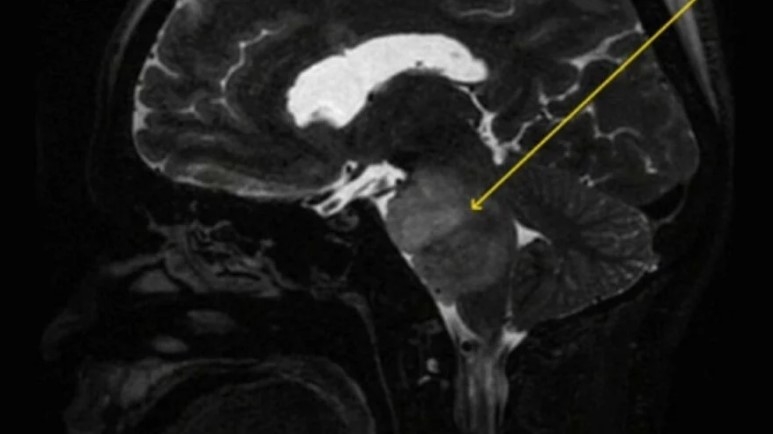

Gizemli hastalığının temeline inmek için hastaya beyin taramaları yapıldı.

Sonuçlar, Hintli adamda, oldukça agresif ve tedavisi zor bir beyin tümörü tipi olan intrinsik pontin gliomu olduğunu ortaya çıkardı. Adamın hıçkırıklarının, tümör tedavisi görmeye başladıktan sonra azalmaya başladığı açıklandı.

Bir dizi kan testi ve fizik muayeneden hemen yanıt gelmemesinin ardından, sağlık görevlileri adamı CT taramasından geçirmeye karar verdi. Burada ise beyninde bir lezyon tespit edildi. Ardından sağlık görevlileri adamı daha ayrıntılı bir MRI taramasından geçirdiler.